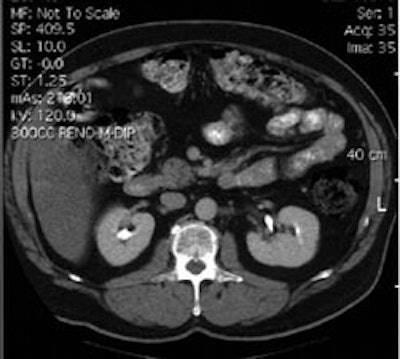

Recurrent colorectal carcinoma: The patient shown below had a history of colon cancer and was being evaluated for a rising CEA-level. CT scan had been interpreted as negative. The OncoScint exam demonstrated focal abnormal tracer activity within the mid-abdomen (red arrows). This activity persistent on delayed images following administration of a bowel prep. At surgery the patient was found to have omental disease and involved lymph nodes corresponding to the abnormality on the OncoScint exam. Even in retrospect, the CT images did not demonstrate definitive abnormality (Click CT for more images) |